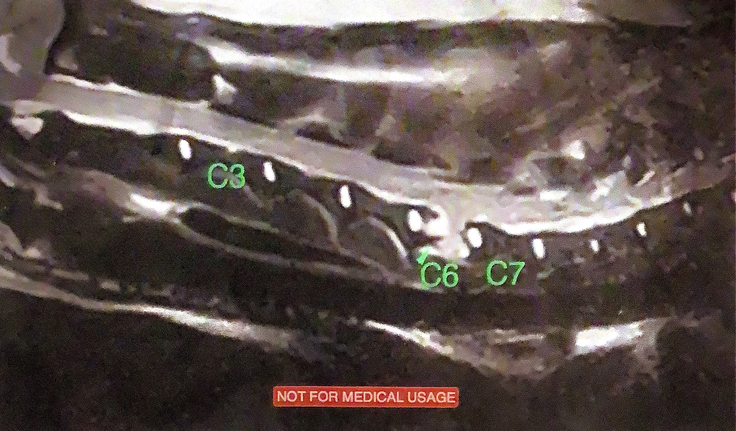

夜間救急にすぐに連れて行きレントゲン撮影をしてもらいましたが、原因は不明でした。翌日かかりつけ医に朝一番で行って診察してもらいましたが、頸椎ヘルニアの可能性があると言われMRI撮影が必要とされました。浜松市ではすぐに撮影してくれる病院はなく、静岡県島田市に撮影をしてくれる病院を探し出し検査後、

首の6番の骨が癌に侵されて骨が変形してしまい神経を圧迫していると

膝から崩れ落ちてしまう程の診断を聞かされました。何もしなければ余命3ヵ月と宣告されました。足に麻痺が出て自らの意思で排尿することができなくなりそれからずっと麻痺したままです。時々ですが、うれしい時には後ろ脚が少しだけ、動きます、頭部にはダメ-ジがないため表情はまだ豊です。これが又、すごく切なく、何とかしなくては!という思いななりました

頸椎C6のMRIです。